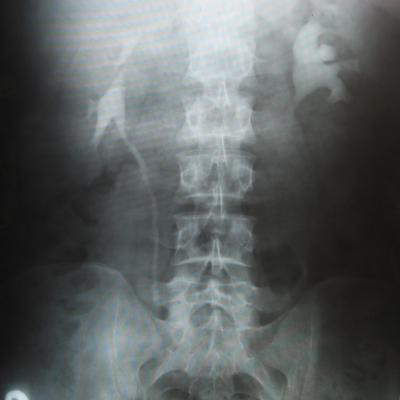

Посев мочи на флору и чувствительность к антибиотикам проводил - роста флоры не выявлено. Результаты урографии: http://s50.radikal.ru/i130/1005/fc/38ec99eeac78.jpg

У Вас гидронефротическая трансформация левой почки. Необходимо проведение ретроградной пиелографии в условиях урологического стационара. При обнаружении камня в мочеточнике - показано его лечение.